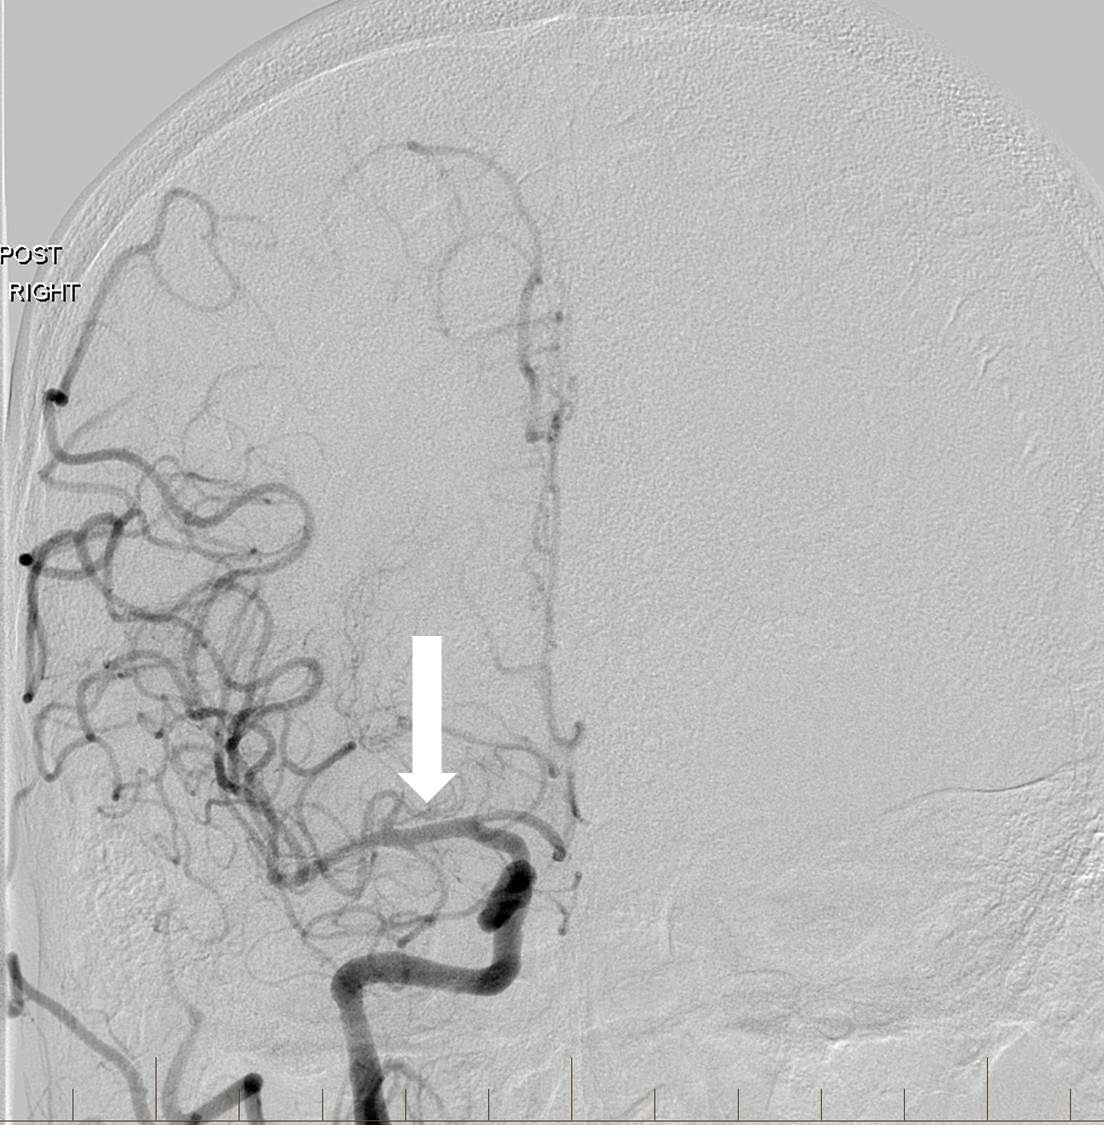

The right MCA and right anterior cerebral arteries (ACAs) could not be visualized, and multifocal embolic filling defects were detected within the cavernous and supraclinoid ICA segments on microcatheter contrast injection past the carotid origin occlusion (Figure 7).